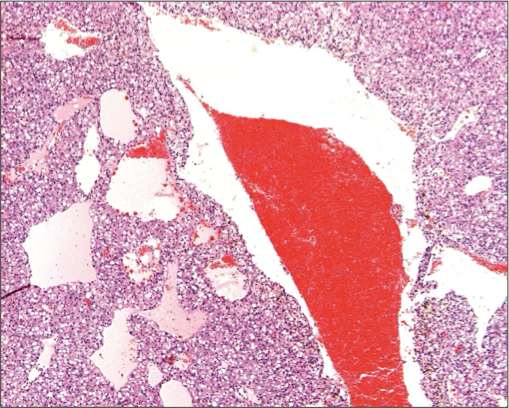

What tumour is this?

Seminoma

Gross: white and soft replaced most testicular parenchyma

Hx: can be diffuse or intertubular (this one is diffuse), large round poorly differentiated cells

Benign